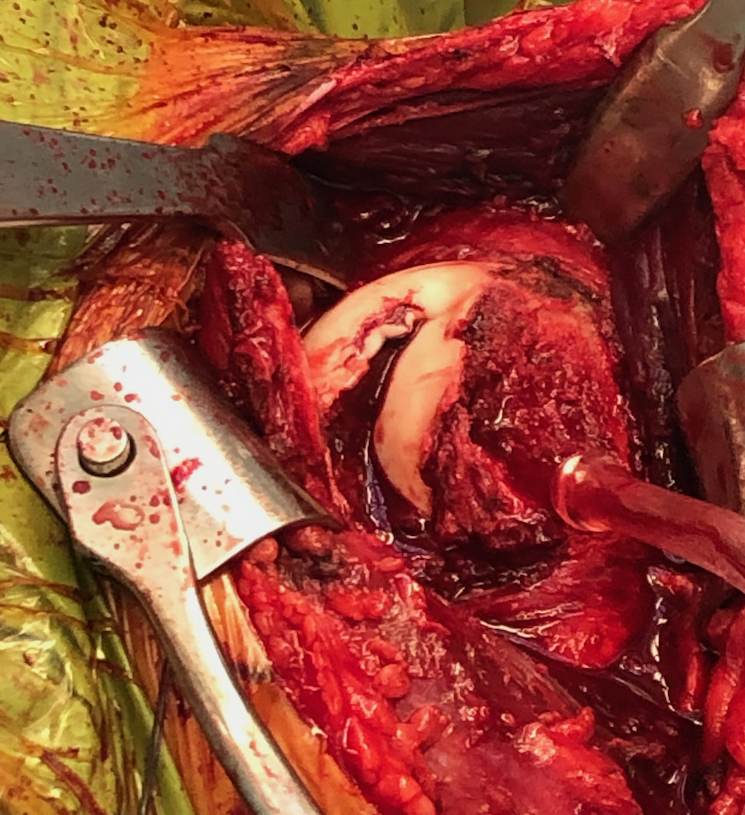

Technique

Anterior deltopectoral approach - reduce humeral head

Address bony defects

- reverse Hill Sachs / anterior humeral head defect

- posterior bony bankart

Subscapularis +/- Lesser tuberosity transfers

Indications

Defects 25%

Options

McLaughlin - subscapularis transfer into defect / makes defect extra-articular

Neer modification - lesser tuberosity + subscapularis transfer into defect

Technique

Case 1: Lesser tuberosity osteotomy, removal comminuted articular fragment, insertion osteochondral allograft

Case 2: Osteochondral allograft with anchor repair of subscapularis